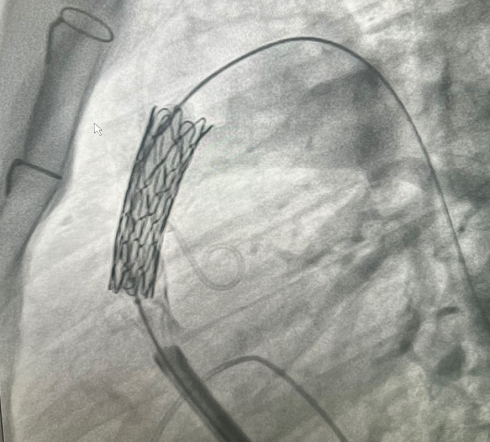

– Нам доступны клапаны с размерной линейкой от 2 до 3-х сантиметров. Клапан можно имплантировать, если размер выводного тракта и самого кондуита – места, куда надо ставить клапан – от 2 до 3-х см. Если диаметр меньше, то клапан будет кальцинироваться, тромбироваться, створки перестанут работать и снова произойдёт стеноз, – пояснил рентгенэндоваскулярный хирург Михаил Комиссаров. |

У пациента из Луганской Народной Республики просвет ранее имплантированного кондуита составлял 1,5 сантиметра, поэтому рентгенхирурги на первом этапе расширили его методом баллонной дилатации. При этом был риск разрыва сосуда, поэтому, чтобы избежать возможных осложнений, медики сначала имплантировали стентграфт – металлический каркас, покрытый герметичным полимером. Просвет кондуита удалось расширить до необходимого диаметра. Затем через бедренную вену хирурги доставили к сердцу искусственный биологический клапан лёгочной артерии Myval индийского производства.

– Новый клапан прослужит несколько лет. Что особенно важно, в дальнейшем можно будет выполнить малоинвазивную процедуру имплантации клапана по технологии «стент в стент», – отметил заведующий кардиохирургической службой. |